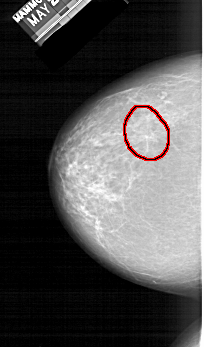

A_1410_1.LEFT_CC

LEFT_CC LINES 5551 PIXELS_PER_LINE 3256 BITS_PER_PIXEL 12 RESOLUTION 43.5 OVERLAY

FILE: A_1410_1.LEFT_CC.OVERLAY

TOTAL_ABNORMALITIES 1

ABNORMALITY 1

LESION_TYPE MASS SHAPE ARCHITECTURAL_DISTORTION MARGINS ILL_DEFINED

ASSESSMENT 4

SUBTLETY 2

PATHOLOGY BENIGN

TOTAL_OUTLINES 1

BOUNDARY